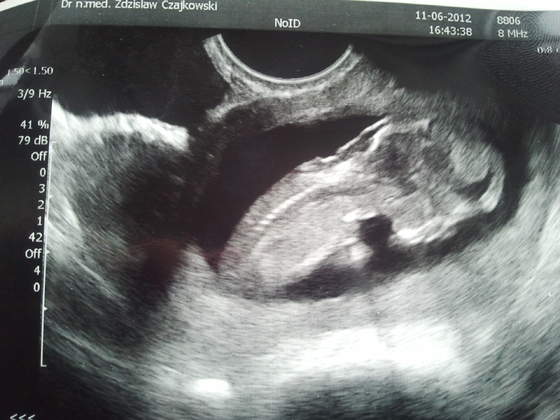

Dziewczynki zdjęcia wstawiać